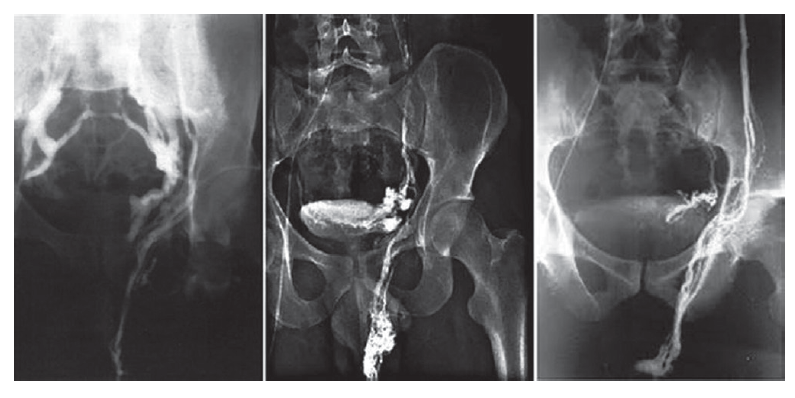

H. Sakamoto и Y. Ogawa (2008) исследовали взаимосвязь между варикоцеле и простатическим венозным сплетением у 209 мужчин (средний возраст — 35,3 года). По данным скротальной доплерэхографии у 68 мужчин варикоцеле не было выявлено, у 94 было одностороннее варикоцеле и 47 имели двусторонние варикоцеле. Средний диаметр простатического венозного сплетения и пиковая скорость антеградного кровотока в простатическом венозном сплетении были выше у мужчин с двусторонним варикоцеле и ниже у больных с односторонним варикоцеле и у тех, у кого варикоцеле не было выявлено (р < 0,01). Мужчины с односторонним варикоцеле имели большую среднюю пиковую скорость антеградного кровотока, чем те, у кого варикоцеле не было выявлено (р < 0,05). У всех мужчин диаметр простатического венозного сплетения положительно коррелировал с диаметром правого и левого лозовидного сплетения (р < 0,0001). Таким образом, было установлено, что варикоцеле, особенно двустороннее, связано с венозными аномалиями простаты [56]. Опубликованы результаты флебографии, во время которой контрастирование гроздевидного сплетения на отсроченных снимках сопровождалось контрастированием вен простатического и пузырного сплетения (рис. 17) [57].

Рис. 17. Ретроградная почечная флеботестикулография. Контрастирование парапростатического венозного сплетения на стороне варикоцеле. Слева — преобладает сброс через внутреннюю подвздошную вену. Посередине и справа — преобладает сброс через вену семявыносящего протока